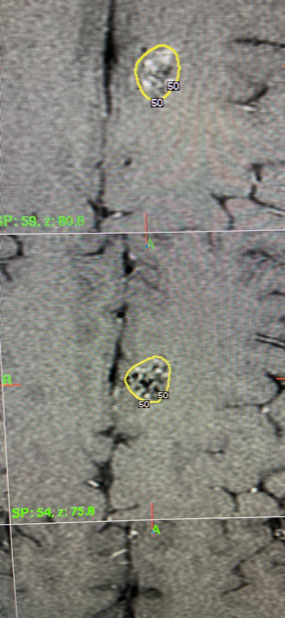

Several weeks after the hemorrhage, the patient was brought for definitive treatment of her Brain AVM with Gamma Knife. On the day of the procedure, she underwent Brain MRI and angiogram to localize the AVM nidus. A plan was made to treat the nidus with 24Gy to the 50% isodose line (Figure 5). The 50% isodose line was created to be very tight to the AVM nidus and encompassed a volume of 1.3 cubic cm. The patient tolerated the procedure well and was discharged the same day.

Fig. 5